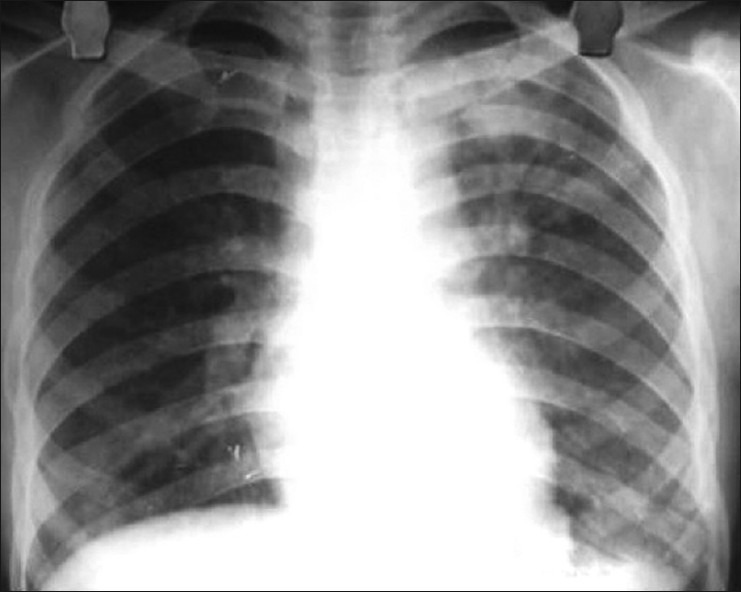

Рентген

Опасным воспалением при туберкулезе или пневмонии считается верхнедолевой очаг поражения, который чаще всего поражается микобактериями.

При пневмонии обнаруживаются на рентгене изменения, позволяющие отличить ее от туберкулеза:

- Уплотнение (инфильтрация) участка легких с неявными, размытыми очертаниями или в виде дымки (характерно для снимков при острой форме).

- Усиление легочного рисунка (при интерстициальной форме).

При верхнедолевой левосторонней пневмонии поражается до 5 долей легкого. Заболевания этого органа протекают тяжелее, чем правосторонняя пневмония, при которой поражается 1-3 участка.

Флюорографией при пневмонии чаще выявляется поражение нижних и средних частей с изменениями корня легкого.

При туберкулезном инфицировании изменения отмечаются в верхней части легкого, отличаются четкими очертаниями, без видимых изменений корня.

На рентгенограмме обнаруживается при туберкулезе:

- Диссеминированном. Множество мелких, хорошо очерченных, или более крупных пятен, есть каверны.

- Очаговом. Уплотнение находится не ниже 2 ребра, вокруг могут быть фиброзные тяжи, усилен легочный рисунок.

- Инфильтративном. Уплотнения правильной округлой формы на рентгеновском снимке в верхней легочной доле.

- Казеозной пневмонии. Множество полостей распада с неровными краями, очагами отсева, смещением средостения в больную сторону груди.

Рентгеновские снимки на сегодняшний день являются самым надежным методом в постановке диагноза заболеваний легких. Их поражение присутствует в обоих случаях, однако картина существенно различается.

Рассмотрим основные отличия этих заболеваний на снимках:

- Локализация поражений легочной ткани. При пневмонии инфильтративные тени, характеризующие очаги поражения, просматриваются, как правило, в 3, 4, 5, 7, 8, 9 долях легкого, преимущественно поражая нижние участки. Туберкулез, в свою очередь, имеет одностороннюю локализацию, в большинстве случаев поражая правую долю легких в 1, 2, 6 сегментах.

- Очертания теней. При пневмонии инфильтраты (рентгеновские тени) имеют размытые, нечеткие очертания. В острый период заболевания затемнение напоминает дымку, а по мере развития воспаления интенсивность теней возрастает, но нечеткий характер краев сохраняется. Туберкулез же имеет тени с выраженным четким рисунком.

Форма теней. Очаги поражения при пневмонии, как правило, округлой, неправильной, кольцевидной или веретенообразной формы. Площадь поражения зависит от формы заболевания:

- очаговые тени имеют белый цвет и в диаметре не превышают полутора сантиметров, бывают в начале заболевания или при выздоровлении,

- долевая форма характеризуется полным поражением доли легкого,

- сегментарные тени – инфильтрация определенного сегмента,

- крупозная форма – самый тяжелый вариант, при котором воспаляются оба легких, сопровождается различными множественными очагами теней с обеих сторон органов.

Инфильтраты при туберкулезе зависят от формы данного заболевания:

- Диссеминированный туберкулез сопровождается множественными мелкими очагами до 2 мм в диаметре,

- Очаговый , имеет один или несколько теней округлой, эллиптической, реже вытянутой формы с низкой интенсивностью, при которой очаги поражений темнее костной ткани,

- Казеозная форма является самой тяжелой и сопровождается затемнением нескольких долей или даже целого легкого, тень изменяется по мере распада от менее интенсивной до более выраженной,

- Кавернозный , характеризуется очаговым затемнением с просветом посередине (каверна).

Рентгеновские снимки может верно интерпретировать только специалист, имеющий опыт работы в данной области.

Как правило, при постановке диагноза туберкулеза с помощью рентгена необходимо уметь отличать его от рака легкого и пневмонии. Часто разницы на снимках пневмонии и туберкулеза, особенно при инфильтративной форме, практически нет. Однако есть и некоторые отличия. Пневмония обычно представляет собой одностороннее поражение, в то время как туберкулез в большинстве случаев поражает легочную ткань с двух сторон.

Кроме того, инфильтрат при пневмонии локализуется в нижних отделах, а при туберкулезе — в верхних. Инфильтрат более выражен при туберкулезе, часто имеются очаги деструкции, диссеминации.